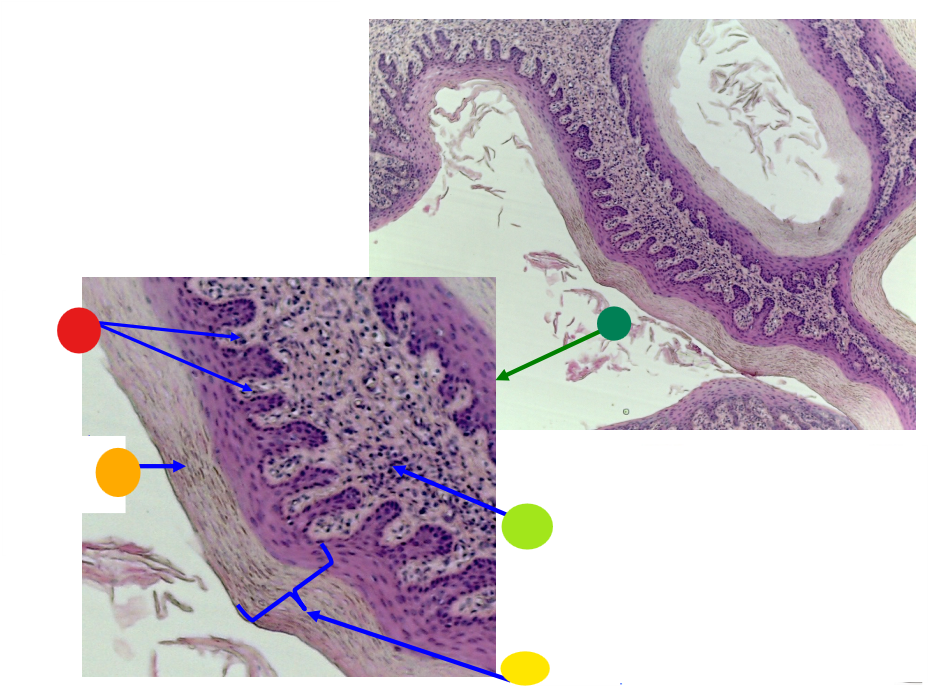

red

tunica albuginea

orange

primordial follicles

yellow

follicular cells

light green

primary oocyte

dark green

granulosa cells

light blue

primary follicles

what is this?

ovary

red

primordial follicles

red

primary follicles

red

tunica albuginea

orange

primary oocyte

yellow

primordial follicles

red

granulosa cells

orange

primary oocyte

what is this

primary follicle

red

tunica albuginea

orange

primordial follicles

red

primary follicle

orange

secondary follicles

what is this

tertiary follicle